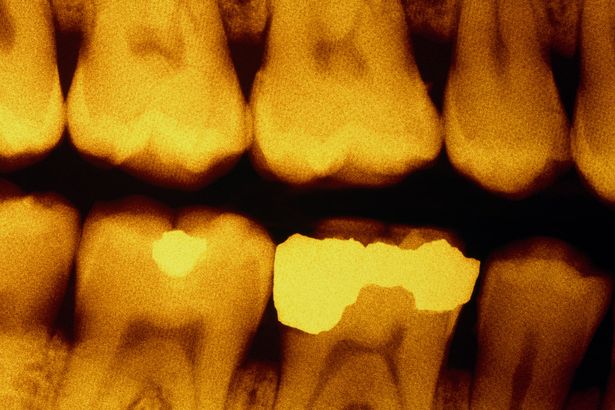

牙齿是由不同的组织层所形成。最外层是珐瑯,是坚硬的白色表面。里面接着是象牙质,扮演支撑珐瑯。中心是牙髓,是包含血管和神经的内部软组织。在蛀牙期间,细菌会分解珐瑯,露出象牙质,增加感染风险,可能甚至露出敏感的牙髓。